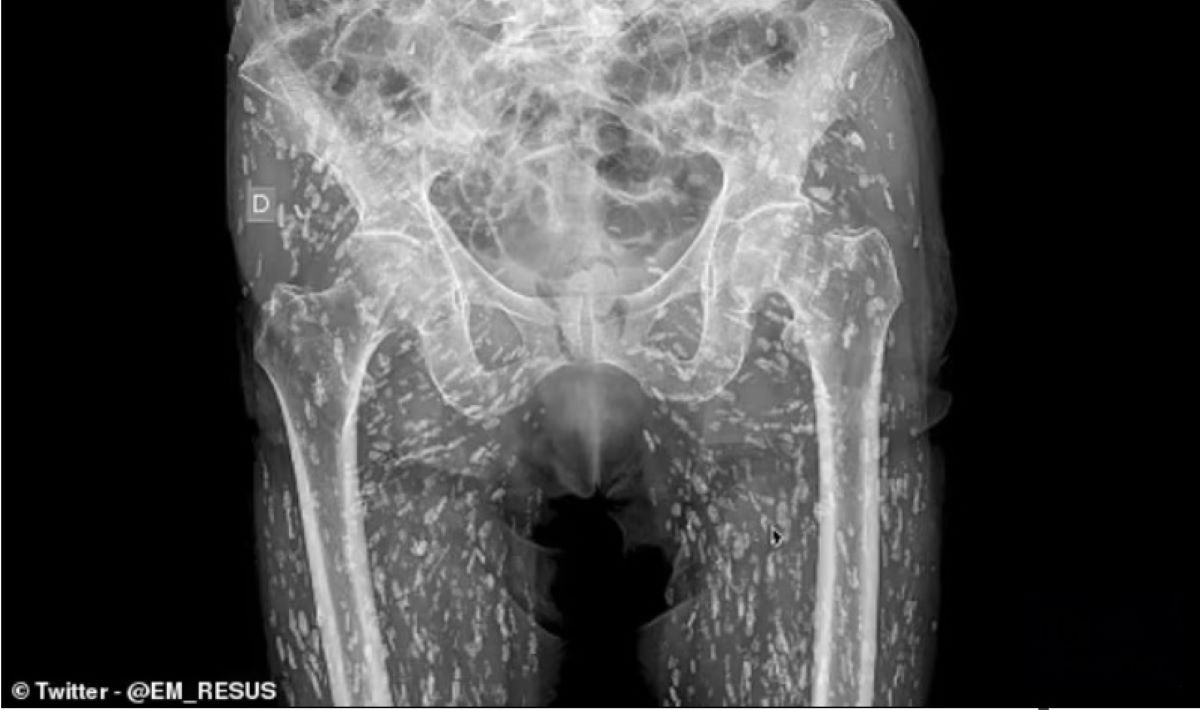

O radiografie realizată după o căzătură banală a scos la iveală o situație medicală rară și înfricoșătoare. Un bărbat din Florida avea corpul plin de chisturi parazitare, consecința consumului de carne de porc crudă sau gătită superficial.

Pacientul ajunsese la spital pentru o durere de șold, însă investigația imagistică a arătat în țesuturile sale moi numeroase formațiuni dense, distribuite ca niște „boabe de orez”. Diagnosticul: cisticercoză, o infecție cauzată de larvele teniei Taenia solium.

Medicul a explicat că transmiterea s-a produs prin consumul de carne de porc insuficient gătită, contaminată cu larve. În astfel de cazuri, organismul nu are nicio barieră în calea parazitului, iar larvele migrează în mușchi, ochi sau creier, unde formează chisturi.

Diagnosticul se pune cu ajutorul radiografiei, CT, RMN și a analizelor serologice.